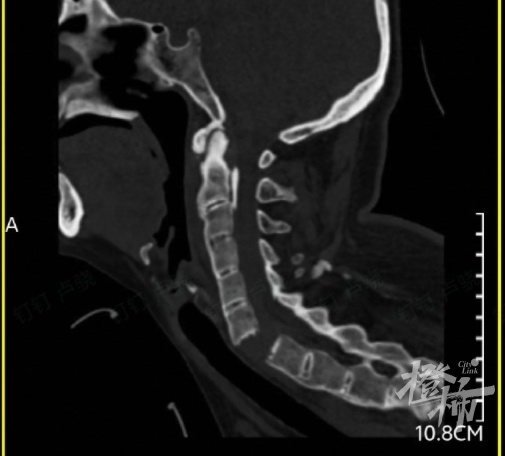

当时,刘女士出现颈部疼痛、四肢无力的症状,紧接着发现自己全身不能活动。随后,她被紧急送往附近的医院救治,通过颈椎影像检查后发现,刘女士颈椎6-7节完全断离,颈椎骨折造成脊髓损伤,导致全身瘫痪。

检查发现,刘女士的颈椎完全断离